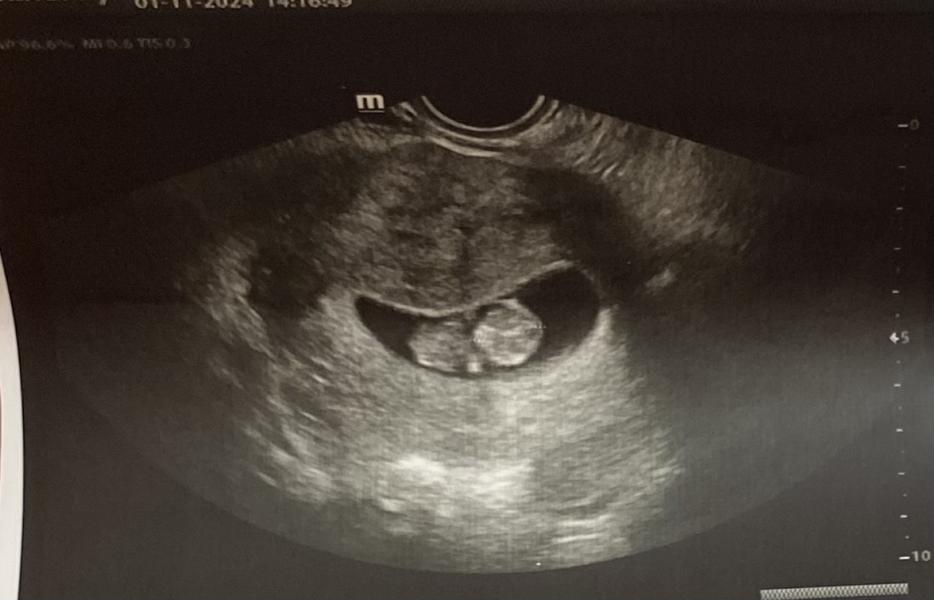

Я была уверена что я не фертильна, ведь кормлю грудью на ежедневной основе! Пошла к доктору чтобы поставить спираль..На узи мне показали «мою спираль» 🤭 10 недель уже.. бывает же..